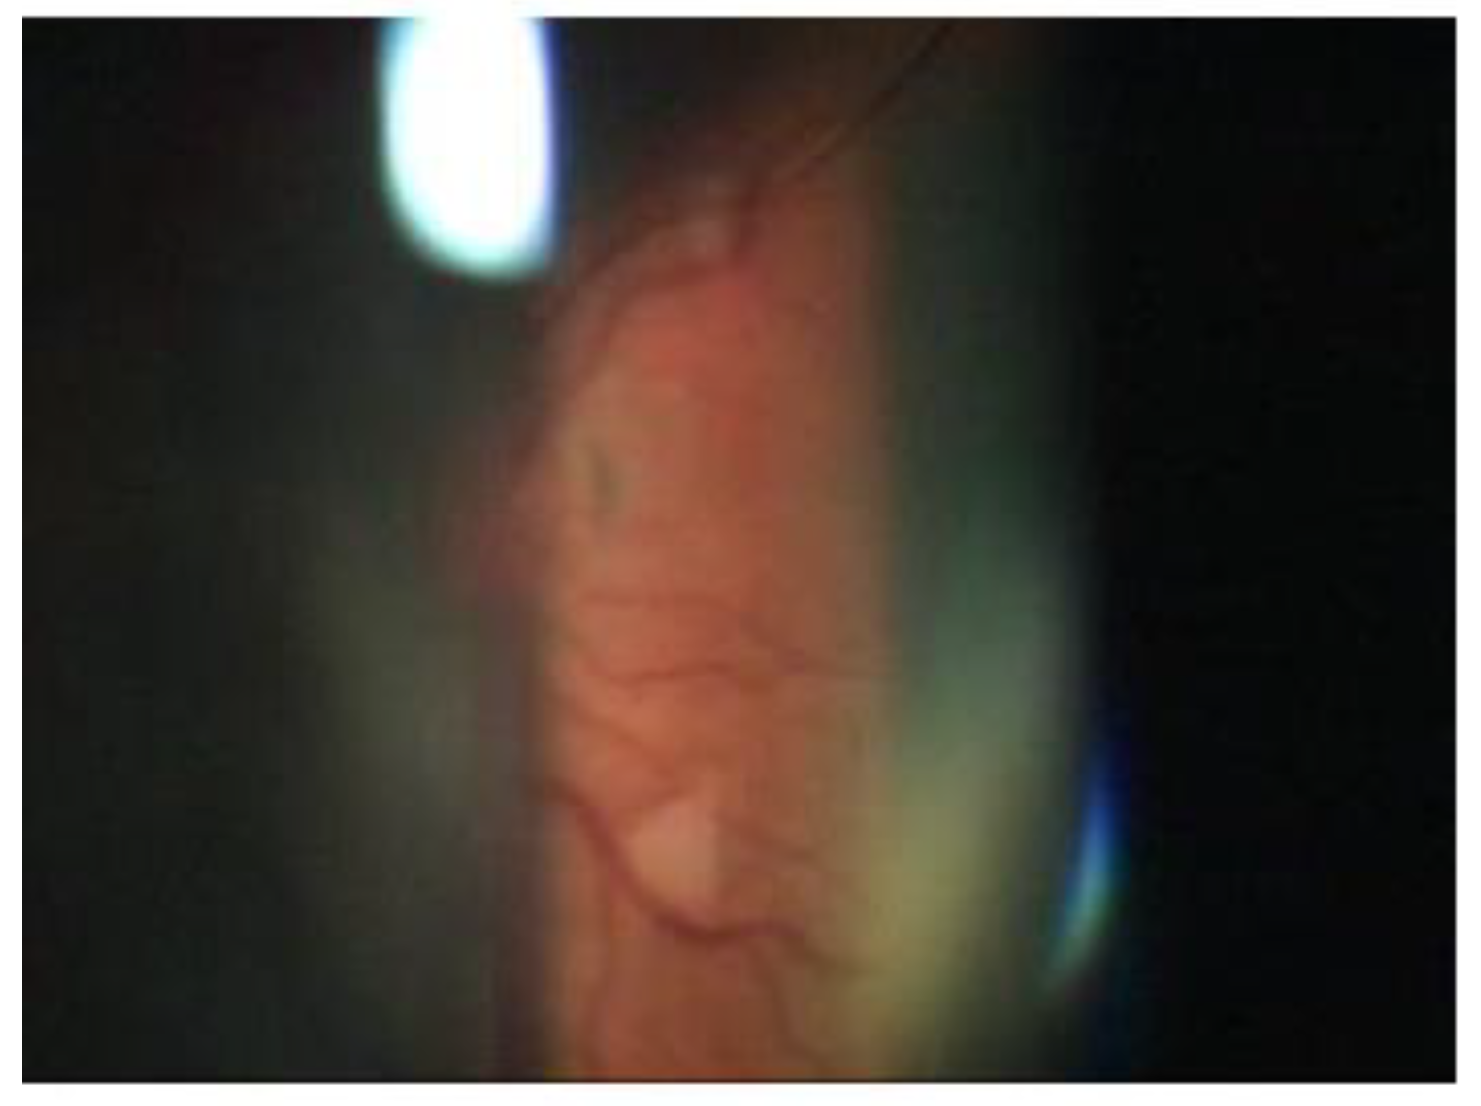

A 65-year-old woman presented to our attention complaining of two days of swelling in the right eye, reduced visual acuity, diplopia, and mild pain. The history was negative for recent trauma and confirmed good general health conditions. The physical examination revealed complete ophthalmoplegia (Figure 1), non-pulsatile reducible axile exophthalmos, eyelid edema, significant chemosis, and conjunctival ectropion (Figure 2). Visual acuity at the time of admission was 5/10 in the right eye and 10/10 in the left eye. The biomicroscopic examination of the anterior segment showed an important stasis of the episcleral vessels (Figure 3) and a shallow anterior chamber, whereas the fellow eye was unremarkable.

Figure 3. Dilatation of the episcleral vessels.

On the third post-operative day, the clinical condition was significantly improved in the following ways: a clear reduction of the exophthalmos and the congestion of the episcleral vessels (Figure 7), a complete recovery of ocular motility (Figure 8), visual acuity improved to 10/10, IOP was 14 mmHg, the disappearance of cotton exudates, and a normalization of the A/V ratio. Fifteen days after the surgery, the ocular conditions were stable.

Figure 7. Resolution of the dilatation of the episcleral vessels, exophthalmos, and ophthalmoplegia.